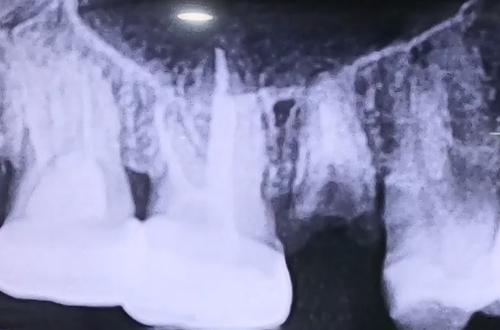

상악동거상술 임플란트 사례

BEFORE

오른쪽 위 작은 어금니가 부러져 내원하셨던 환자분으로,

임플란트를 진행하고자 진료해 보니 깊이가 모자라

뼈이식으로 상악동거상술을 동반하며 임플란트를 진행한 사례입니다.

부러진 치아는 뿌리만 남아 있었고, 뿌리 부분에도 충치가 상당히 심하여

발치 후 당일 즉시 임플란트 치료를 진행한 케이스입니다.